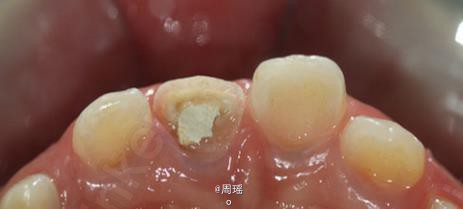

21冠折的树脂充填

男孩,10岁,7个月前外伤致左上门牙冠折,已于我处行根管治疗,现家长要求修复患牙。平素体质很好,无药物、食物过敏史。

树脂充填